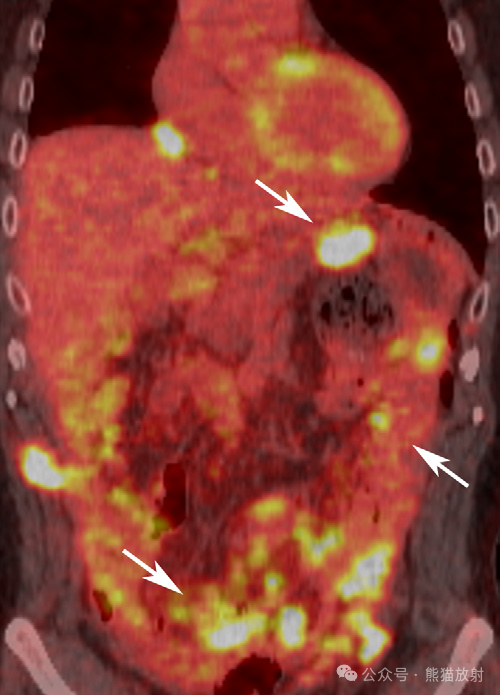

不同类型腹膜间皮瘤两例。(A,B) 46岁男性,湿型上皮样腹膜间皮瘤。腹盆部轴位(A)和冠状 (B) 对比增强 CT 图像显示腹膜不规则增厚,网膜饼形成 (箭)和严重腹水(箭头)。(C,D) 56岁女性,干型上皮样腹膜间皮瘤。腹部轴位增强 CT (C) 和T2WI (D) 图像显示大网膜明显饼状增厚 (箭)。

66岁男性,腹膜间皮瘤,主要累及小肠系膜。腹盆部的轴位 (A) 和冠状 (B) 对比增强 CT 图像显示腹膜结节状增厚(箭)伴小肠系膜片状软组织增厚(箭头),肠系膜呈星芒状表现。